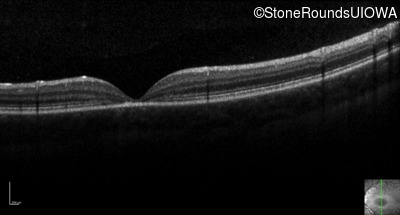

Optical Coherence Tomography - Right - 20/80 -2 sc

Exemplar / OCT Stack